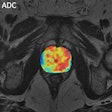

Imaging biomarkers have central role in precision medicine

Texture classification eases lung CT analysis